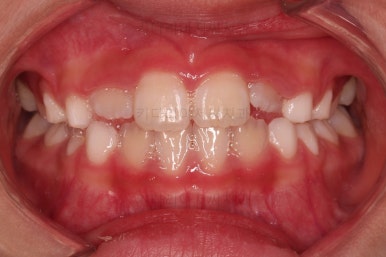

1. 초진

부산어린이교정 키다리아저씨치과에 처음 내원했을 당시의 입안의 모습입니다.

앞니가 거꾸로 물리는 전형적인 앵글씨 3급 부정교합 환아의 모습이었습니다.

아직 유치가 많이 남아 있었꼬, 아래 앞니는 4개가 영구치 맹출, 윗니는 2개가 영구치 맹출 상태였습니다.